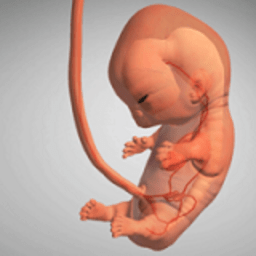

下载

九个月手机版

- 109M